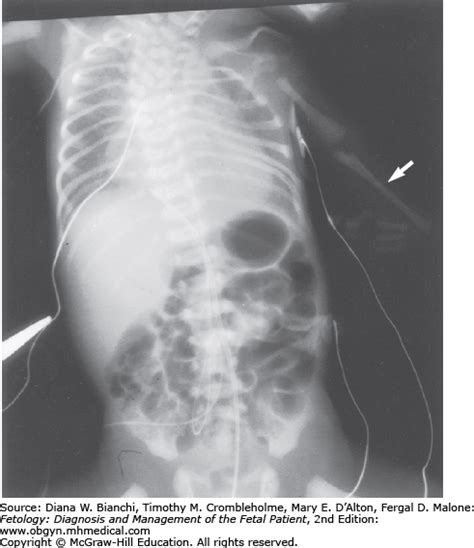

Pyloric Atresia and Stenosis | Obgyn Key